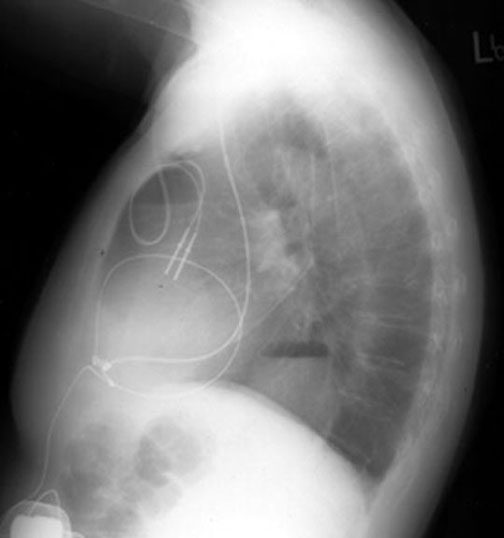

A:   Chest wall pacemaker

B:   Mediastinum: Hiatal hernia

Both  project over lung fields in the lateral view, but can be seen to be in the chest wall and mediastinum in the PA view.